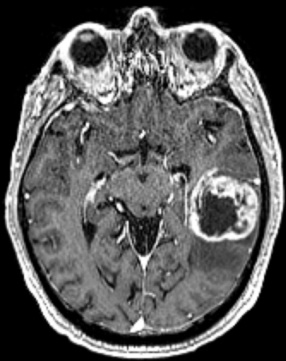

The research, published in Nature Medicine on Aug. 2, 2024, offers new hope and potential treatments for glioblastoma, the most aggressive form of brain cancer.

To discover the pathway cancer cells use to infiltrate the brain, researchers used large-scale gene editing technology to compare gene dependencies in glioblastoma when it was initially diagnosed and after it returned following standard treatments. By doing this, researchers discovered a new pathway used for axonal guidance—a signaling axis that helps establish normal brain architecture—that can become overrun by cancer cells.

“In glioblastoma, we believe that the tumor hijacks this signaling pathway and uses it to invade and infiltrate the brain,” says co-senior author Sheila Singh, professor with McMaster’s Department of Surgery and director of the Center for Discovery in Cancer Research. The research was also co-led by Jason Moffat, head of the Genetics and Genome Biology program at The Hospital for Sick Children (SickKids).